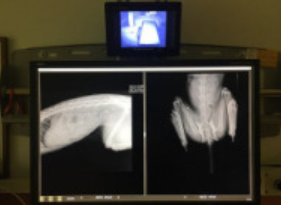

Pierwsze badania - USG, RTG, pobranie krwi nie wykazały żadnych złamań czy urazów wewnętrznych. Ale Czarny nie chodził normalnie, „zawijał” tylnymi nogami, był obolały i przerażony. W końcu pani doktor wpadła na pomysł, aby zbadać mu tętno w łapkach - było słabe. Diagnoza oparta była na naszych przypuszczeniach - najprawdopodobniej Czarny zawiesił się na płocie albo okienku piwnicznym i doszło do obrzęku rdzenia kręgosłupa. Albo miał wypadek samochodowy. Dwa dni nie mógł wrócić, jeść ani pić.